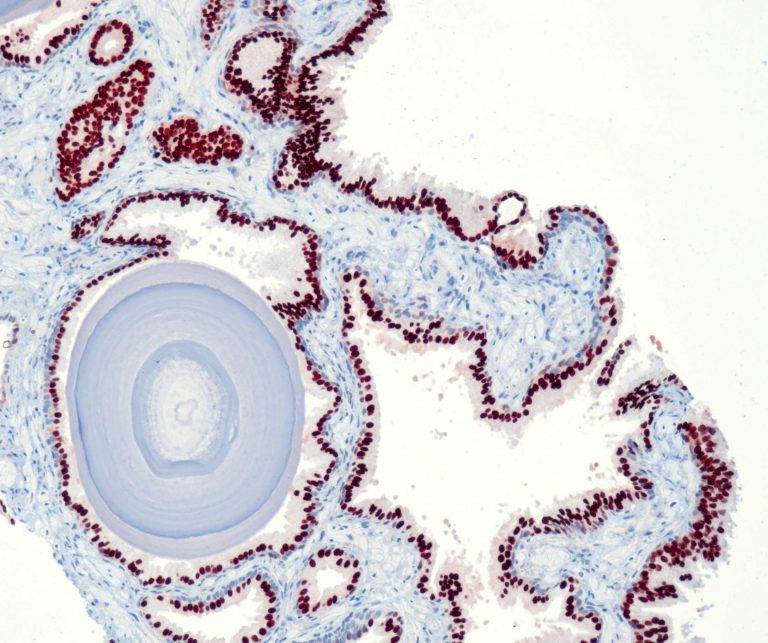

Gynecological Pathology

Gastrointestinal (GI) Pathology

Endocrine Pathology